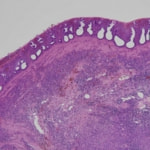

病理組織

症例:ミニチュアダックスフンド、13歳、避妊雌

他院にて肝酵素(GPT、ALP)上昇が認められ、当院にて超音波検査を行うため来院。肝酵素の他にTG、TP、ALBの上昇と、Cre、Naの低下を認めていた。来院時、多飲多尿症状を聴取。肝臓・胆嚢、副腎に対する超音波検査を実施したところ、左側副腎頭側部に由来不明の腫瘤病変を確認。CT検査を行い、左側副腎腫瘍を疑う(腺癌の可能性、血管の巻き込み等ないためオペ推奨)との診断が得られたため、左側副腎腫瘍摘出手術を実施。3.2cm×3.0cm×3.0cmの腫瘤性病変を摘出し、病理検査にて「副腎皮質腺腫(良性腫瘍)」と診断された。術後はホルモン補充としてのステロイド投与は必要なく、肝数値上昇に対する内服薬のみ継続している。数週間で多飲多尿症状も落ち着き、良好な経過を辿っている。